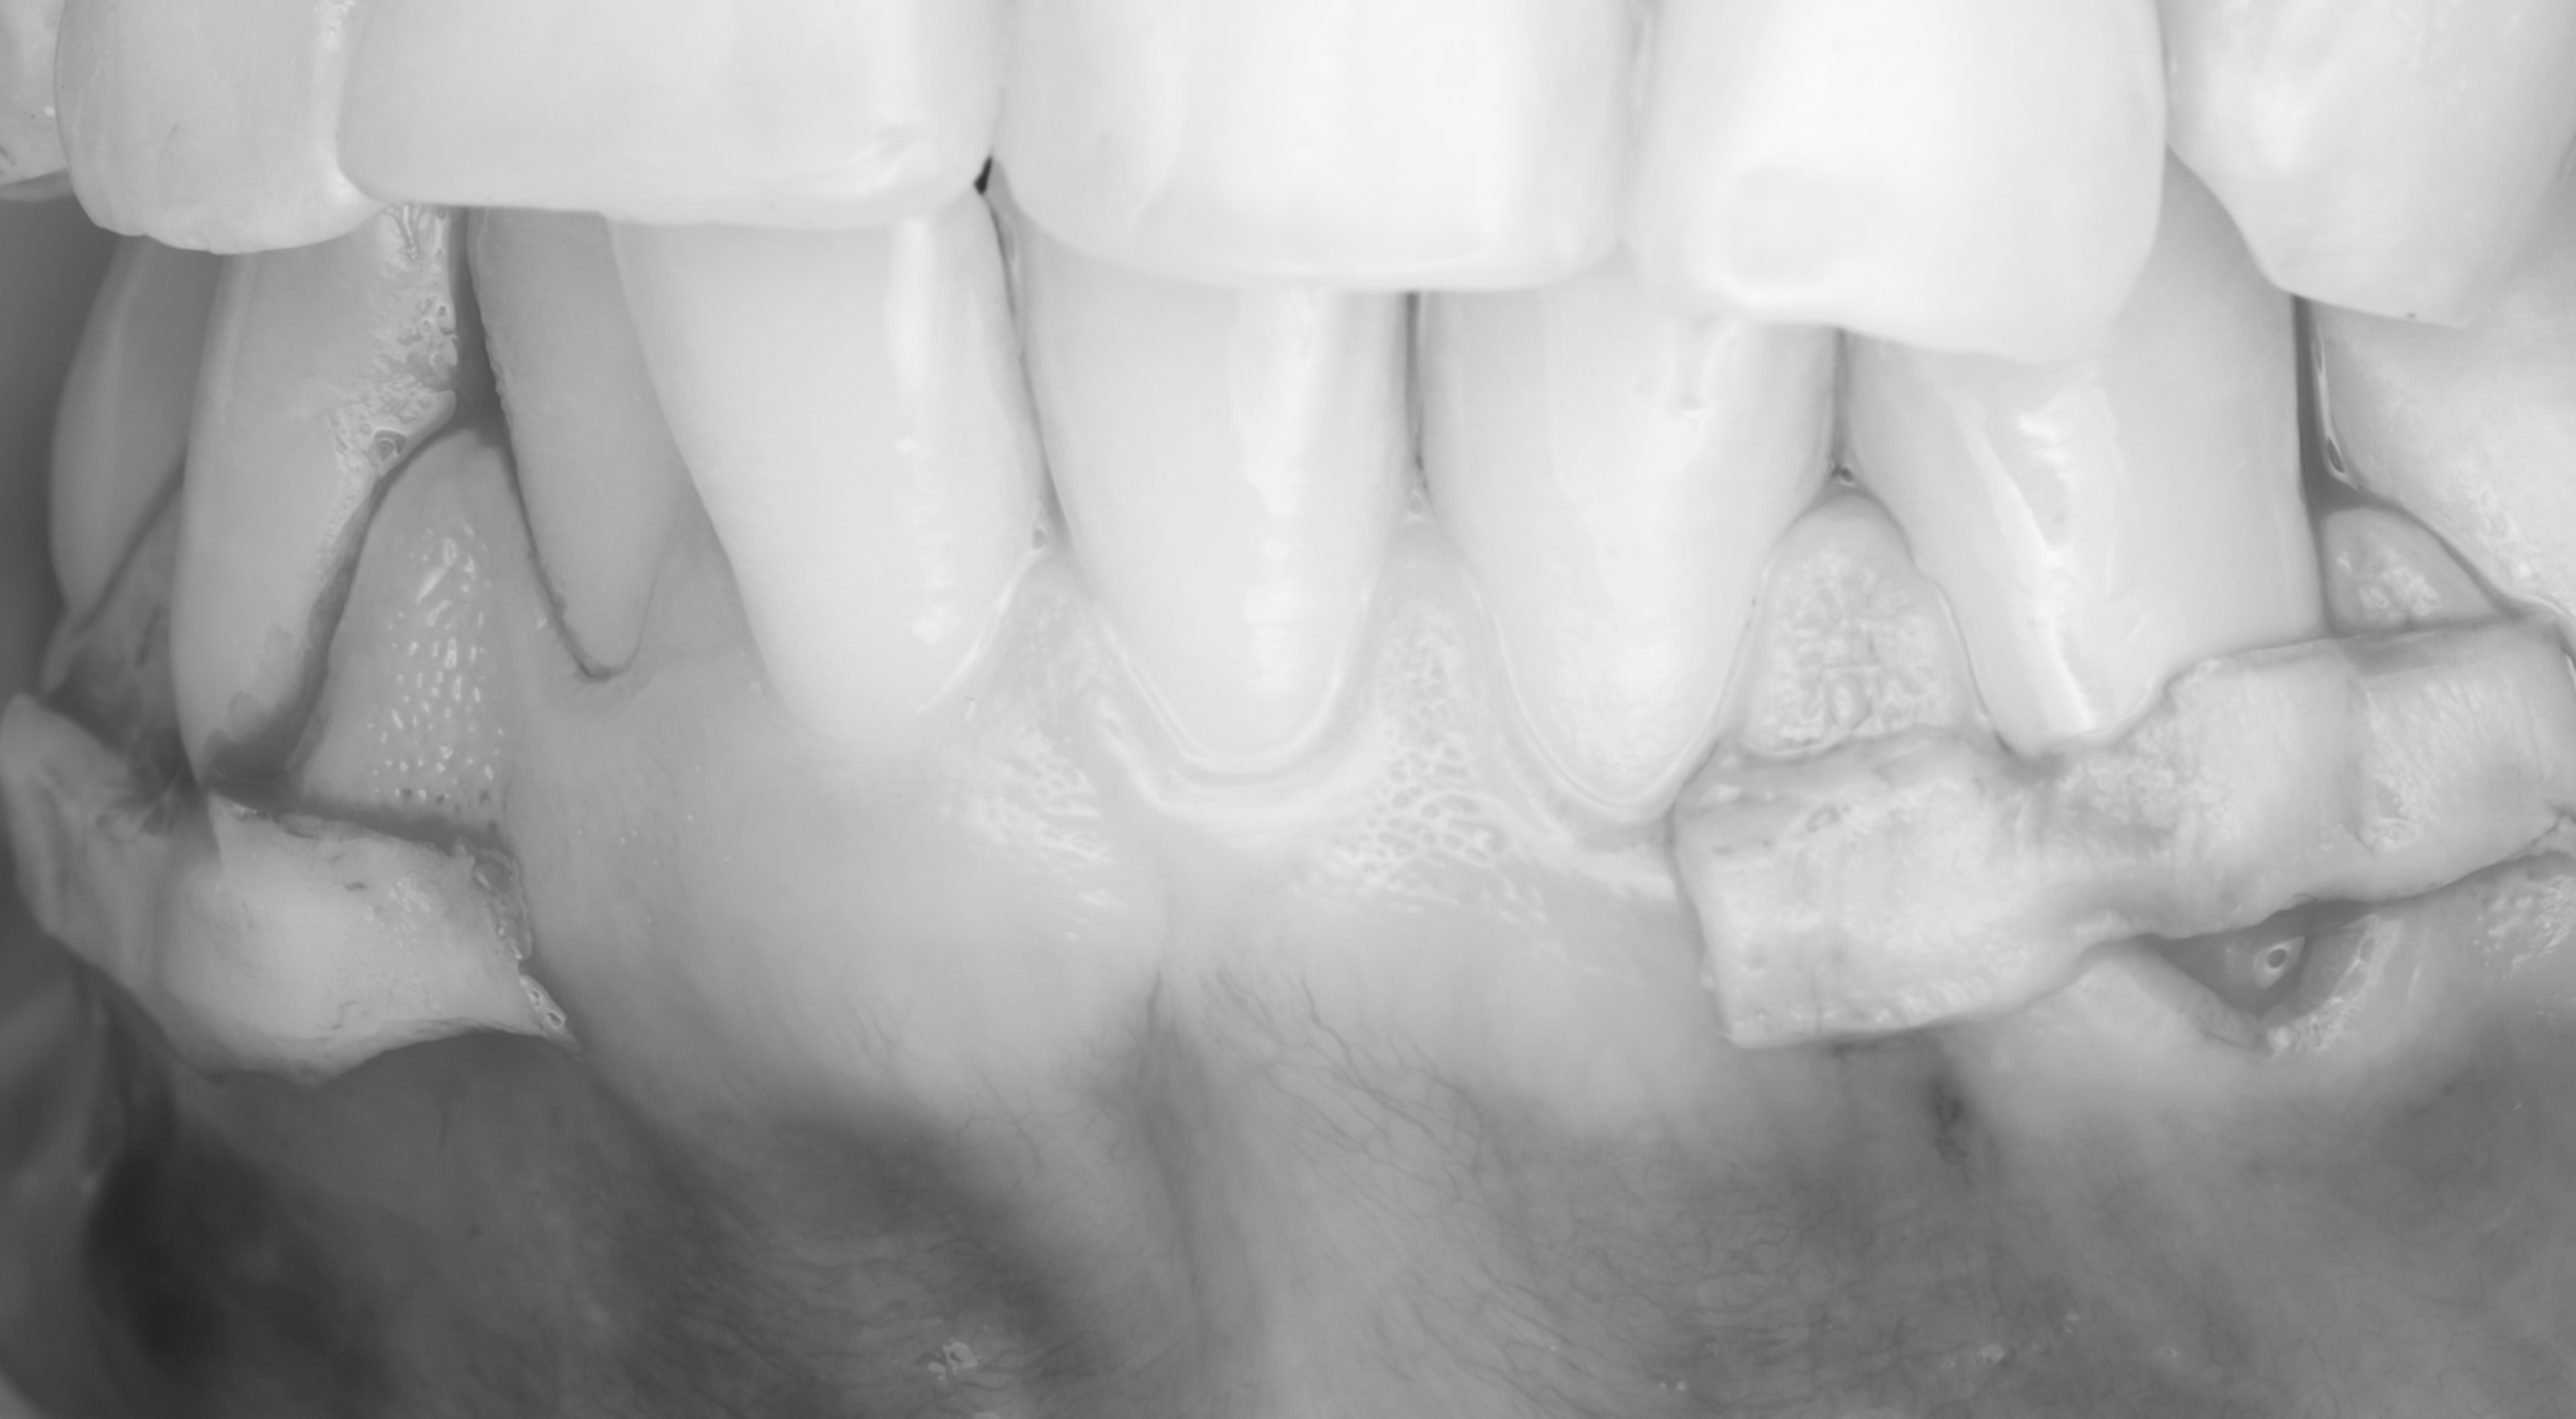

Спустя месяц пациентка с уже санированной полостью рта была направлена на закрытие рецессий. Терапевт произвёл закрытие рецессий десны композитным материалом. Также было запланировано пришлифовывание материала в полости рта и закрытие небольшой рецессии на зубе 4.4.

Операция была выполнена туннельной техникой с получением десневого трансплантата с нёба